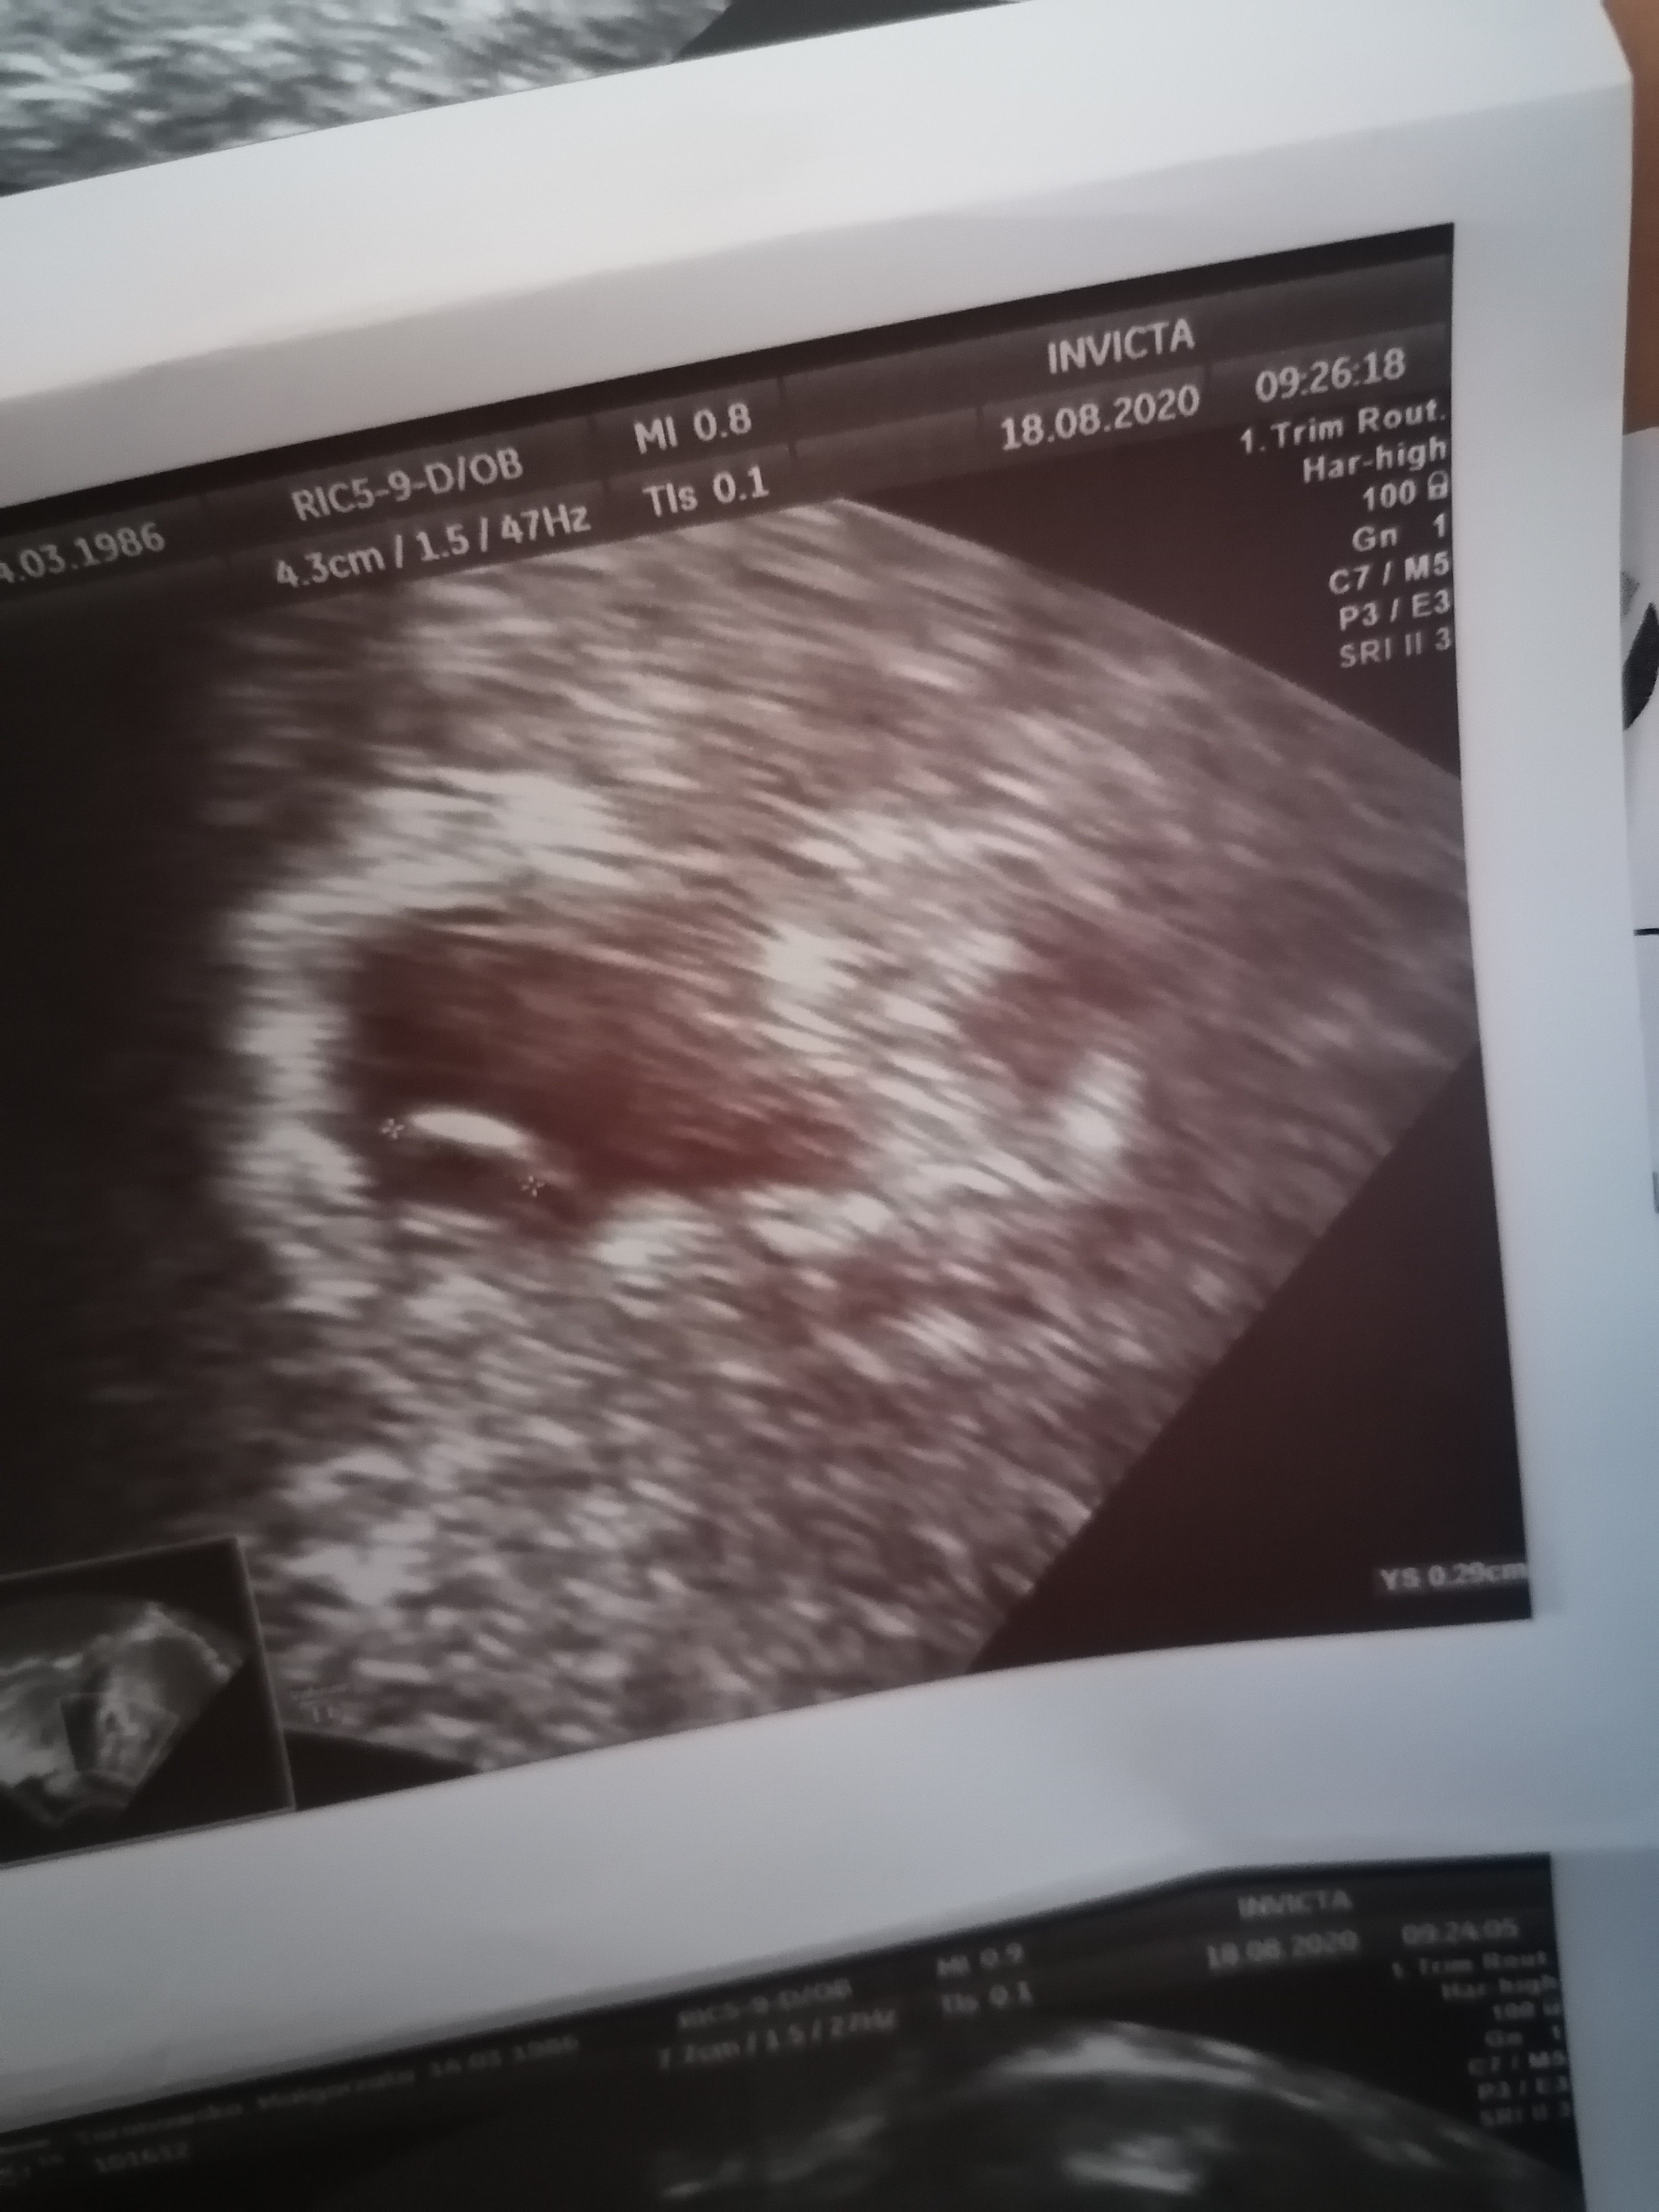

To z piątku